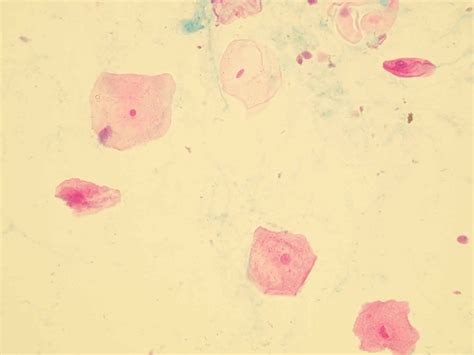

Urine Epithelial Squamous Cells

Urine analysis is a common diagnostic tool used in medical settings to assess various aspects of a patient's health. Among the many components examined in a urine sample, urine epithelial squamous cells play a crucial role in diagnosing certain conditions. These cells, which originate from the squamous epithelium lining the urinary tract, can provide valuable insights into the health of the urinary system. Understanding the significance of urine epithelial squamous cells and their implications in diagnostic processes is essential for healthcare professionals and patients alike.

Urine epithelial squamous cells are flat, scale-like cells that line the distal urethra and the external genitalia. These cells are typically found in small numbers in a normal urine sample. However, an increased presence of these cells can indicate various conditions, including infections, inflammation, or even more serious issues like cancer. The presence of urine epithelial squamous cells in urine samples is often noted during a routine urinalysis, which is a standard test performed to evaluate the overall health of the urinary system.

During a urinalysis, a healthcare provider will examine the urine sample under a microscope to identify and count the number of urine epithelial squamous cells present. The results are typically reported as the number of cells per high-power field (HPF). A normal urine sample may contain a few squamous cells, but an elevated count can indicate a potential issue. The interpretation of these results is crucial for accurate diagnosis and treatment.